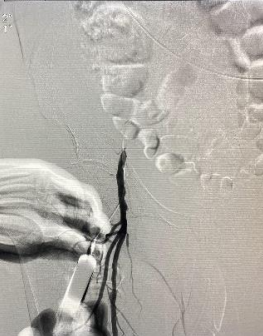

遂果断另辟蹊径,经肱动脉穿刺成功,行腹主动脉造影证实右侧髂总动脉闭塞,左侧髂总动脉极重度狭窄并串珠样改变,故经股动脉入路此路不通。

头颈部血管造影提示:患者为右侧颈内动脉极重度狭窄合并右侧大脑中动脉闭塞。

由远及近,优先开通右侧大脑中动脉恢复颅内血流,再行右侧颈内动脉起始部支架植入血管成形,顺利开通闭塞血管,颅内血流恢复。